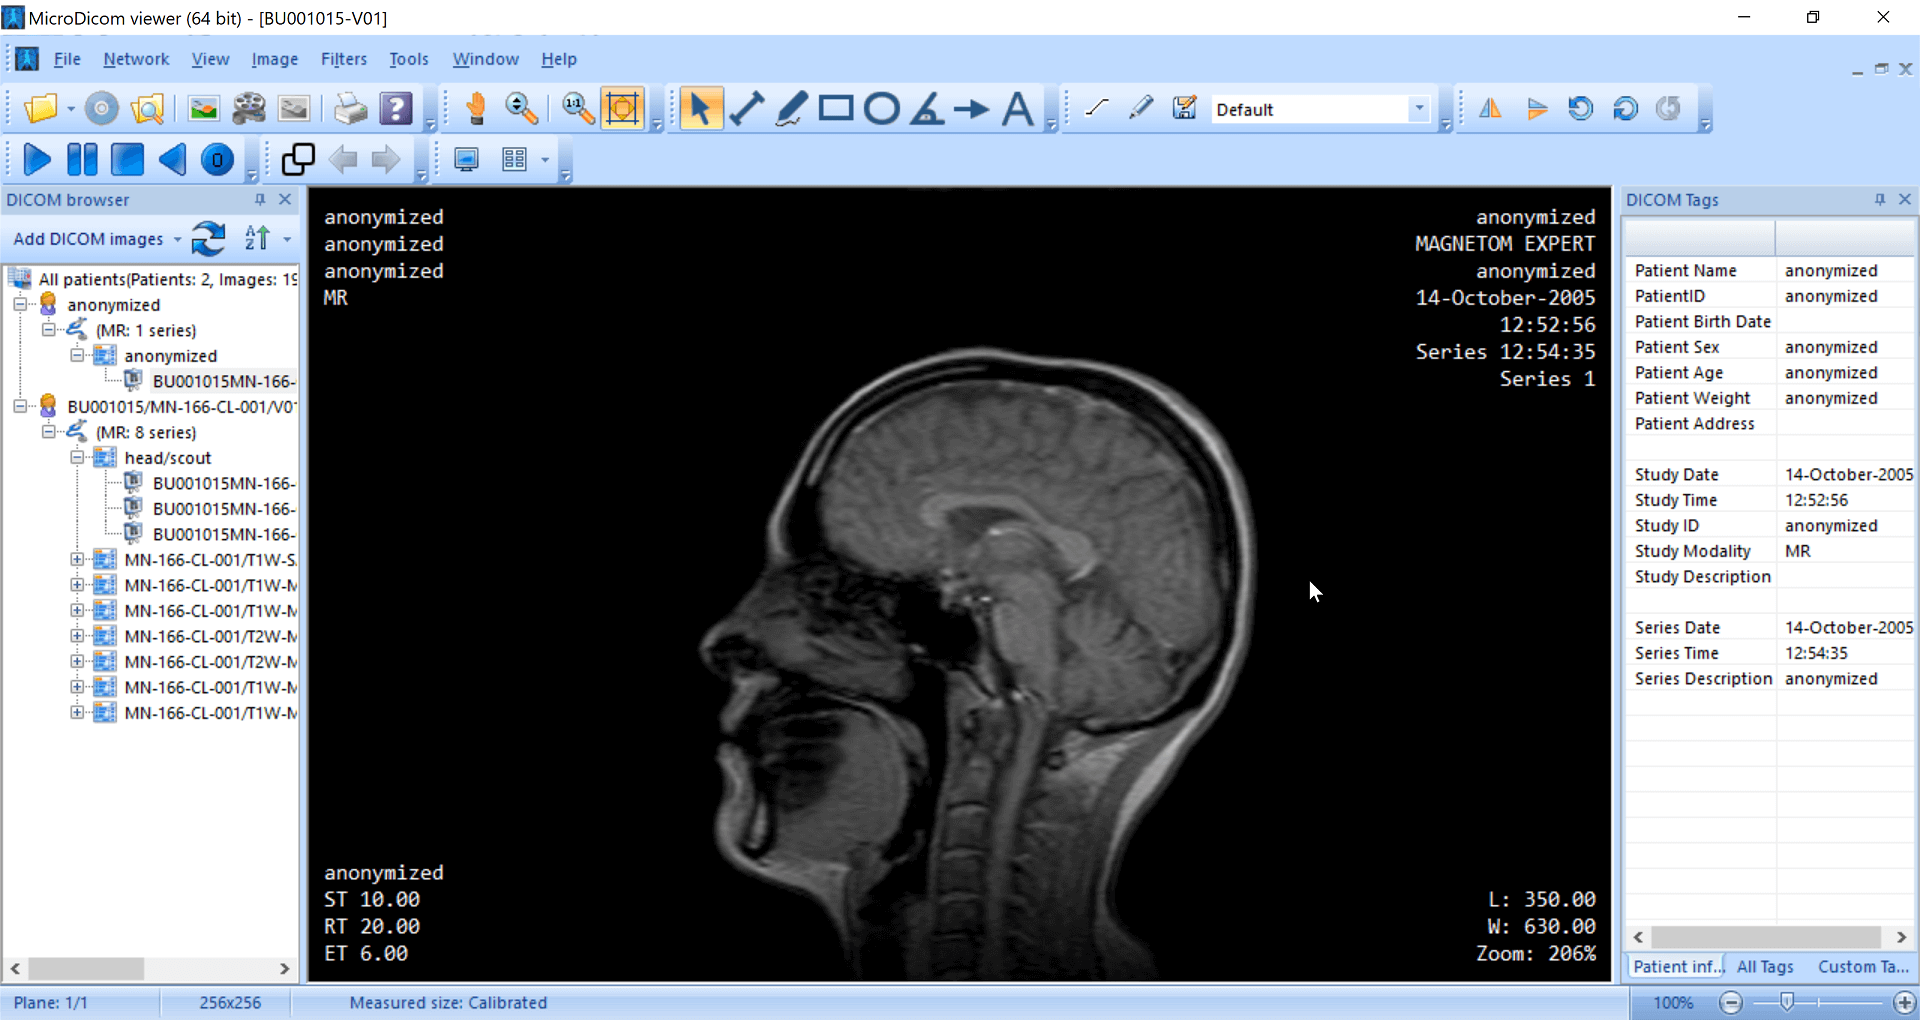

The application allows both viewing and processing of DICOM images. It can generate structured reports, and allows basic measurements, annotations, and zooming in for images. MicroDicom does not offer advanced features such as MPR and volume rendering. It can be downloaded as a potable zip file that does not require installation. This allows it to be used on any device that has a Windows OS.